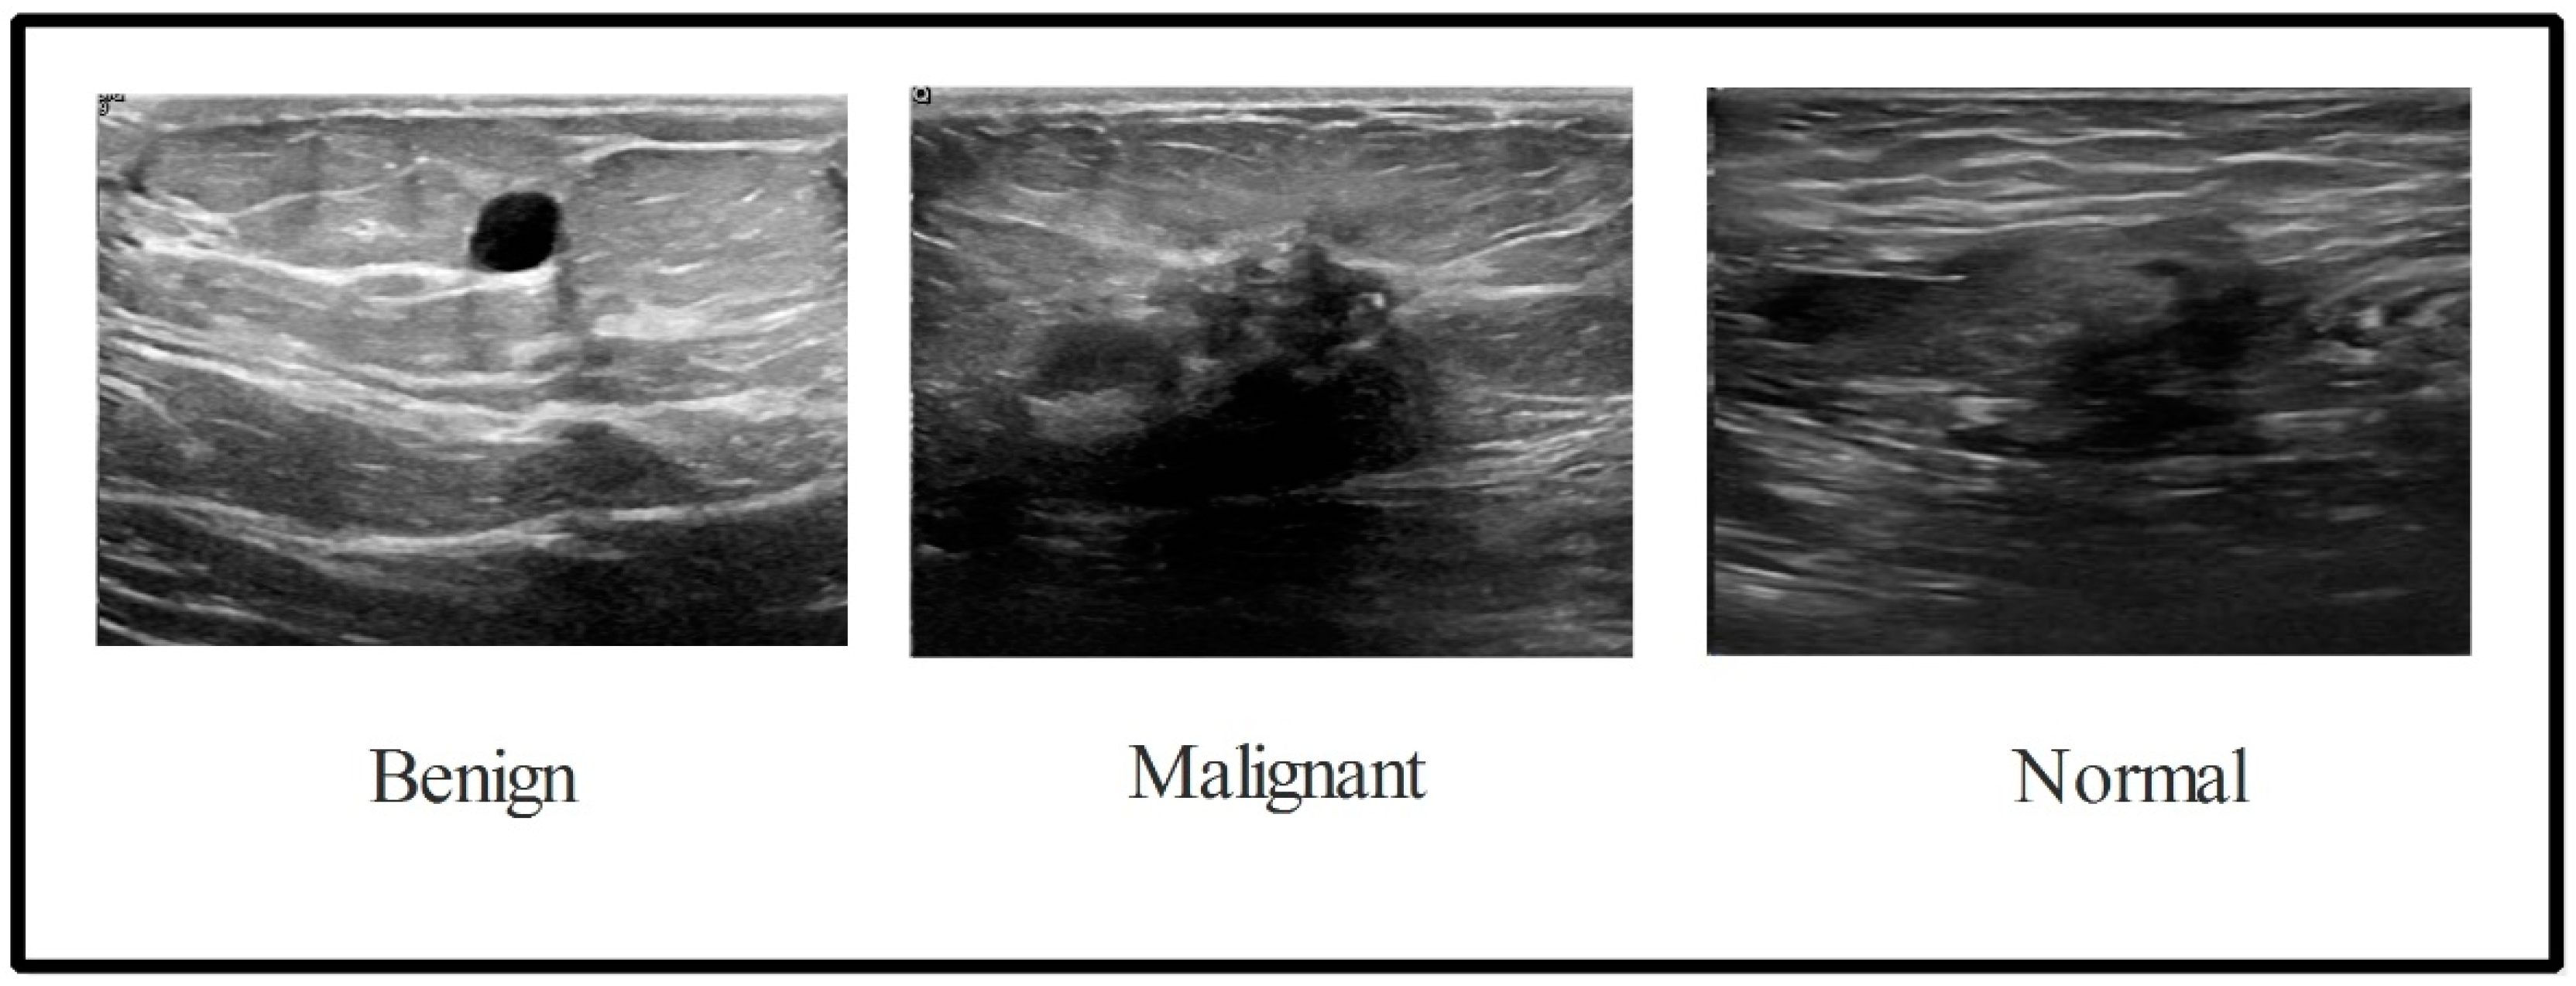

3.1. Dataset Augmentation